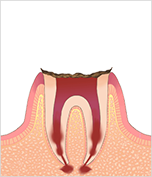

C4 歯根まで達したむし歯

歯根までむし歯に冒された状態。いったん痛みは引きます。多くの場合、抜歯が必要です。抜歯後、入れ歯などで失った歯の機能を補います。

歯根までむし歯に冒された状態。いったん痛みは引きます。多くの場合、抜歯が必要です。抜歯後、入れ歯などで失った歯の機能を補います。